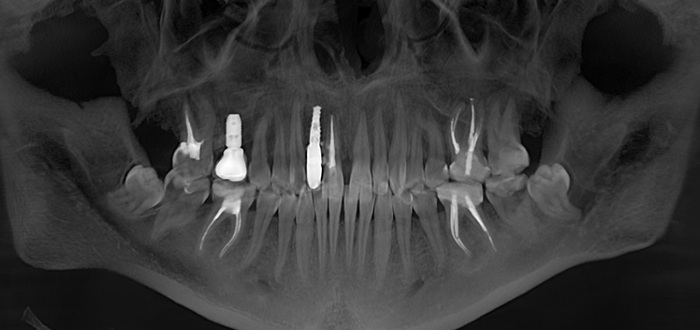

Согласитесь, не особо эстетично. Ортопантомограмма:

Контрольная ортопантомограмма:

Прицельный снимок: